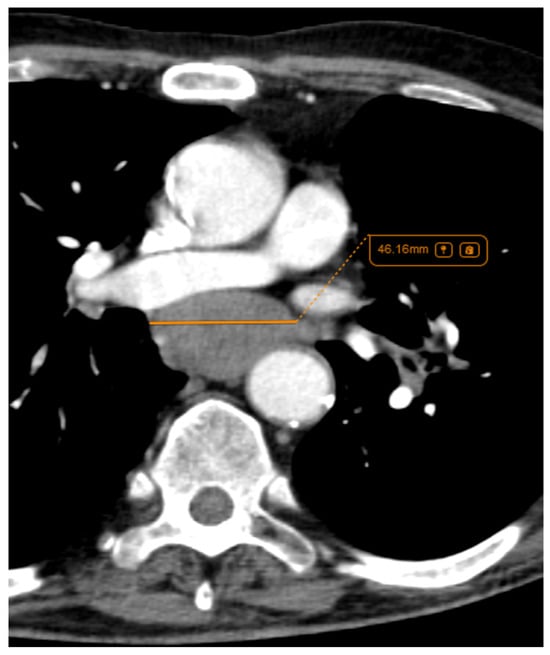

Figure 3.

Axial CT of four different cases of small cell lung cancer: (A) right hilar mass with segmental atelectasis and expansion into the right main bronchus; (B) left voluminous mass with central necrosis, pleural invasion and periaortic extension; (C) small-sized central right tumour with paratracheal location; and (D) central left tumour with important mediastinal invasion involving the pulmonary trunk, left pulmonary artery, left main bronchus, and oesophagus.

Regarding lymph node involvement, there was an equal distribution in the ADC group (50%), while in the SQCC group there was a significantly higher proportion, with 19 cases (87%) presenting with lymph node involvement (Figure 11) with p = 0.02. In the current study, staging was conducted using the criteria of the Eighth Edition Lung Cancer Stage Classification [30]. Some examples of lymph node involvement can be found in Figure 12 and Figure 13.

Figure 11.

Axial and coronal CT of a left central SQCC with multiple mediastinal lymph nodes involving all mediastinal lymph stations.